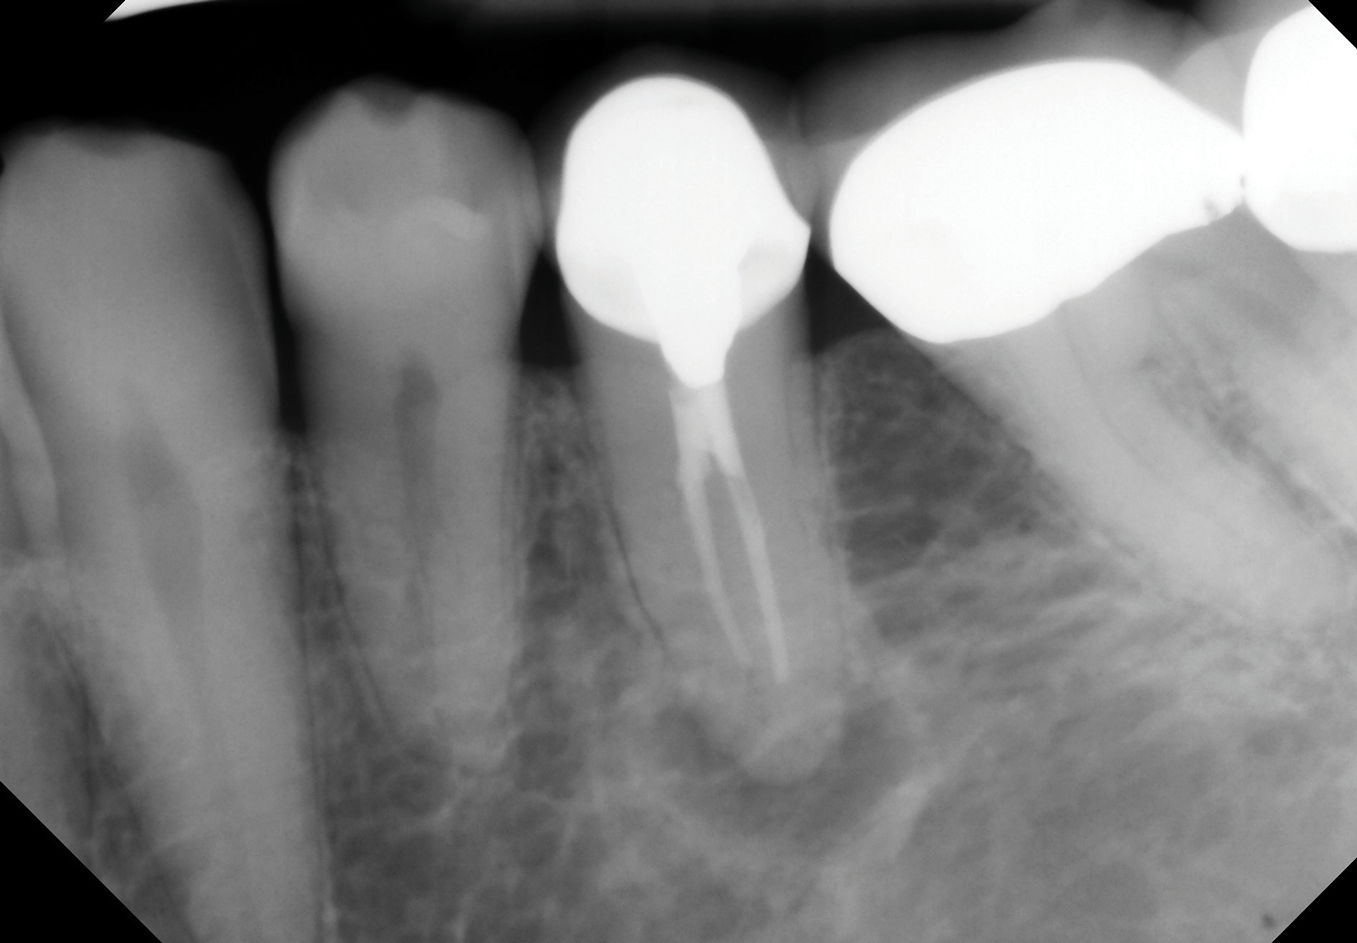

Fig 6. Identifiable inadequate NSRCT is associated with predictable RETX. Fig 6: Preoperative periapical radiograph showing AP, tooth No. 20. Fig 7. Postoperative periapical radiograph. Fig 8. Six-month follow-up periapical radiograph showing a significant decrease in size of the AP.

Fig 7. Identifiable inadequate NSRCT is associated with predictable RETX. Fig 6: Preoperative periapical radiograph showing AP, tooth No. 20. Fig 7. Postoperative periapical radiograph. Fig 8. Six-month follow-up periapical radiograph showing a significant decrease in size of the AP.

Fig 8. Identifiable inadequate NSRCT is associated with predictable RETX. Fig 6: Preoperative periapical radiograph showing AP, tooth No. 20. Fig 7. Postoperative periapical radiograph. Fig 8. Six-month follow-up periapical radiograph showing a significant decrease in size of the AP.

The quality of the initial NSRCT is inversely associated with RETX outcomes, with poorer quality initial treatment tied to more predictable retreatment (Figure 6 through Figure 8).23 Inadequate quality of the initial NSRCT (eg, untreated anatomy, under-instrumentation, ledged and underfilled canals, and overextended obturation) was associated with greater predictability following RETX. However, if clinicians cannot identify and correct the mistakes made in the previous root canal therapy, it becomes more challenging to improve treatment outcomes.23